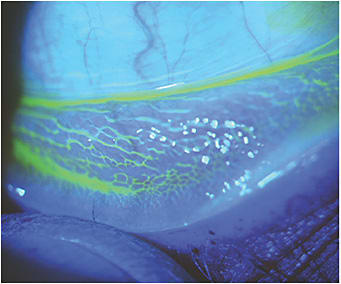

Follicular Conjunctivitis

This photo shows an excellent example of follicular conjunctivitis. This individual presented with a recent history of unilateral ocular irritation and injection that eventually became bilateral. He complained of mild photophobia and discomfort. Palpation of his preauricular nodes revealed moderate tenderness. In addition to the obvious follicular changes, he had grade 1 corneal fluorescein staining. Our initial diagnosis was bilateral follicular conjunctivitis.